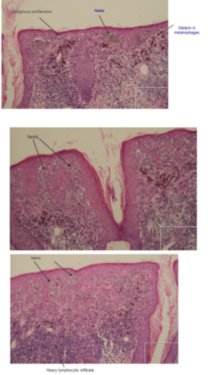

Image Number #3280 (Lentigo Maligna)

Diagnosis: Lentigo Maligna

Description: Pigmented lesion on the ear

This elderly male had a pigmented lesion on his ear which was shown to be a lentigo maligna but surgery was refused. It progressed over 5 years as shown but remained a lentigo maligna or melanoma in situ. There is marked perifollicular pigmentation with black structureless areas where the melanoma has obliterated the follicles. Sometimes the terms annular granular structures and rhomboid figures are used along with asymmetrical perifollicular pigmentation to describe these earlier changes. In truth grey circles are often the earliest features of lentigo maligna particuarly on the face.